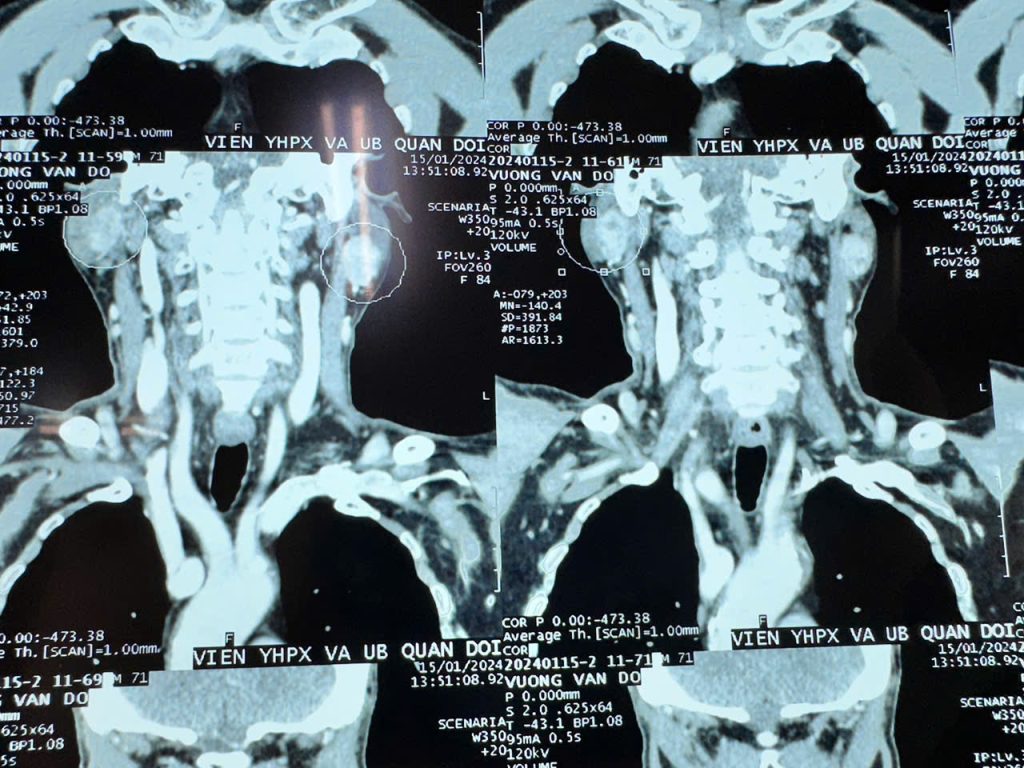

- Hạch cổ tăng kích thước trên siêu âm hoặc các phương tiện chẩn đoán hình ảnh như CT, MRI.

- Hạch có đặc điểm ác tính, như: vi vôi hóa, mất rốn mỡ, tăng sinh mạch bất thường.